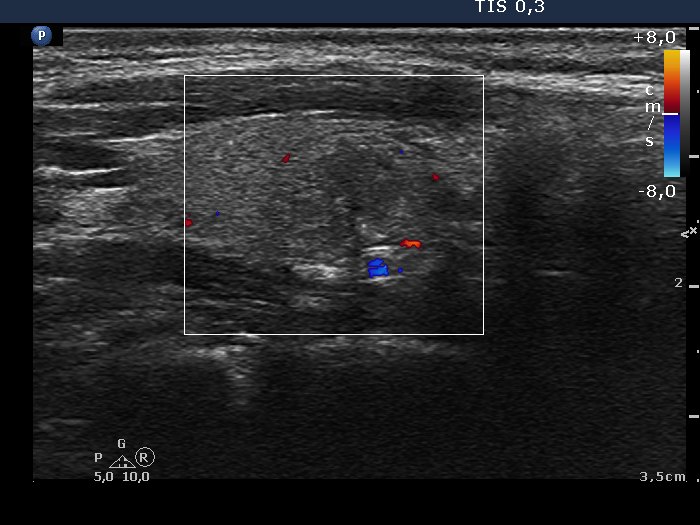

The borders of the nodule - case conp 010 (ultrasonographic picture 5)

Right lobe, longitudinal scan, color Doppler mode.